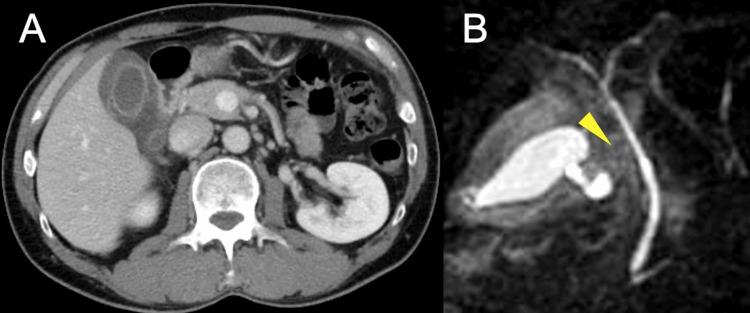

Gallbladder volvulus is a rare but potentially severe condition that requires urgent surgical intervention. This report presents two contrasting cases of gallbladder volvulus with distinct pathogenic mechanisms and degrees of torsion. The first case involves a 97-year-old female who presented with acute symptoms and 270° torsion, leading to complete gallbladder necrosis (Gross type II). The second case involves a 52-year-old male with a subacute presentation and 90° torsion, resulting in incomplete necrosis (Gross type I). Both cases underwent successful laparoscopic cholecystectomy, completed in 69 and 59 minutes, respectively. Analysis of these cases reveals that the degree of torsion correlates with the acuity of presentation and the extent of tissue ischemia, which influences the timing of surgical intervention. This study underscores the importance of early recognition and prompt surgical management in gallbladder volvulus, regardless of presentation pattern. Although gallbladder volvulus predominantly affects elderly females, it can occur across different age groups and genders, highlighting the need for increased clinical awareness to achieve optimal outcomes.

胆囊扭转是一种罕见但可能很严重的病症,需要紧急手术干预。本报告呈现了两例形成对比的胆囊扭转病例,其致病机制和扭转程度各不相同。第一例是一位97岁女性,出现急性症状且有270°扭转,导致胆囊完全坏死(大体类型II)。第二例是一位52岁男性,表现为亚急性症状且有90°扭转,导致不完全坏死(大体类型I)。两例均成功进行了腹腔镜胆囊切除术,分别用时69分钟和59分钟。对这些病例的分析表明,扭转程度与症状的急性程度以及组织缺血程度相关,这会影响手术干预的时机。本研究强调了在胆囊扭转中早期识别和及时手术治疗的重要性,无论其表现形式如何。虽然胆囊扭转主要影响老年女性,但它可发生于不同年龄组和性别,这凸显了提高临床认识以实现最佳治疗效果的必要性。